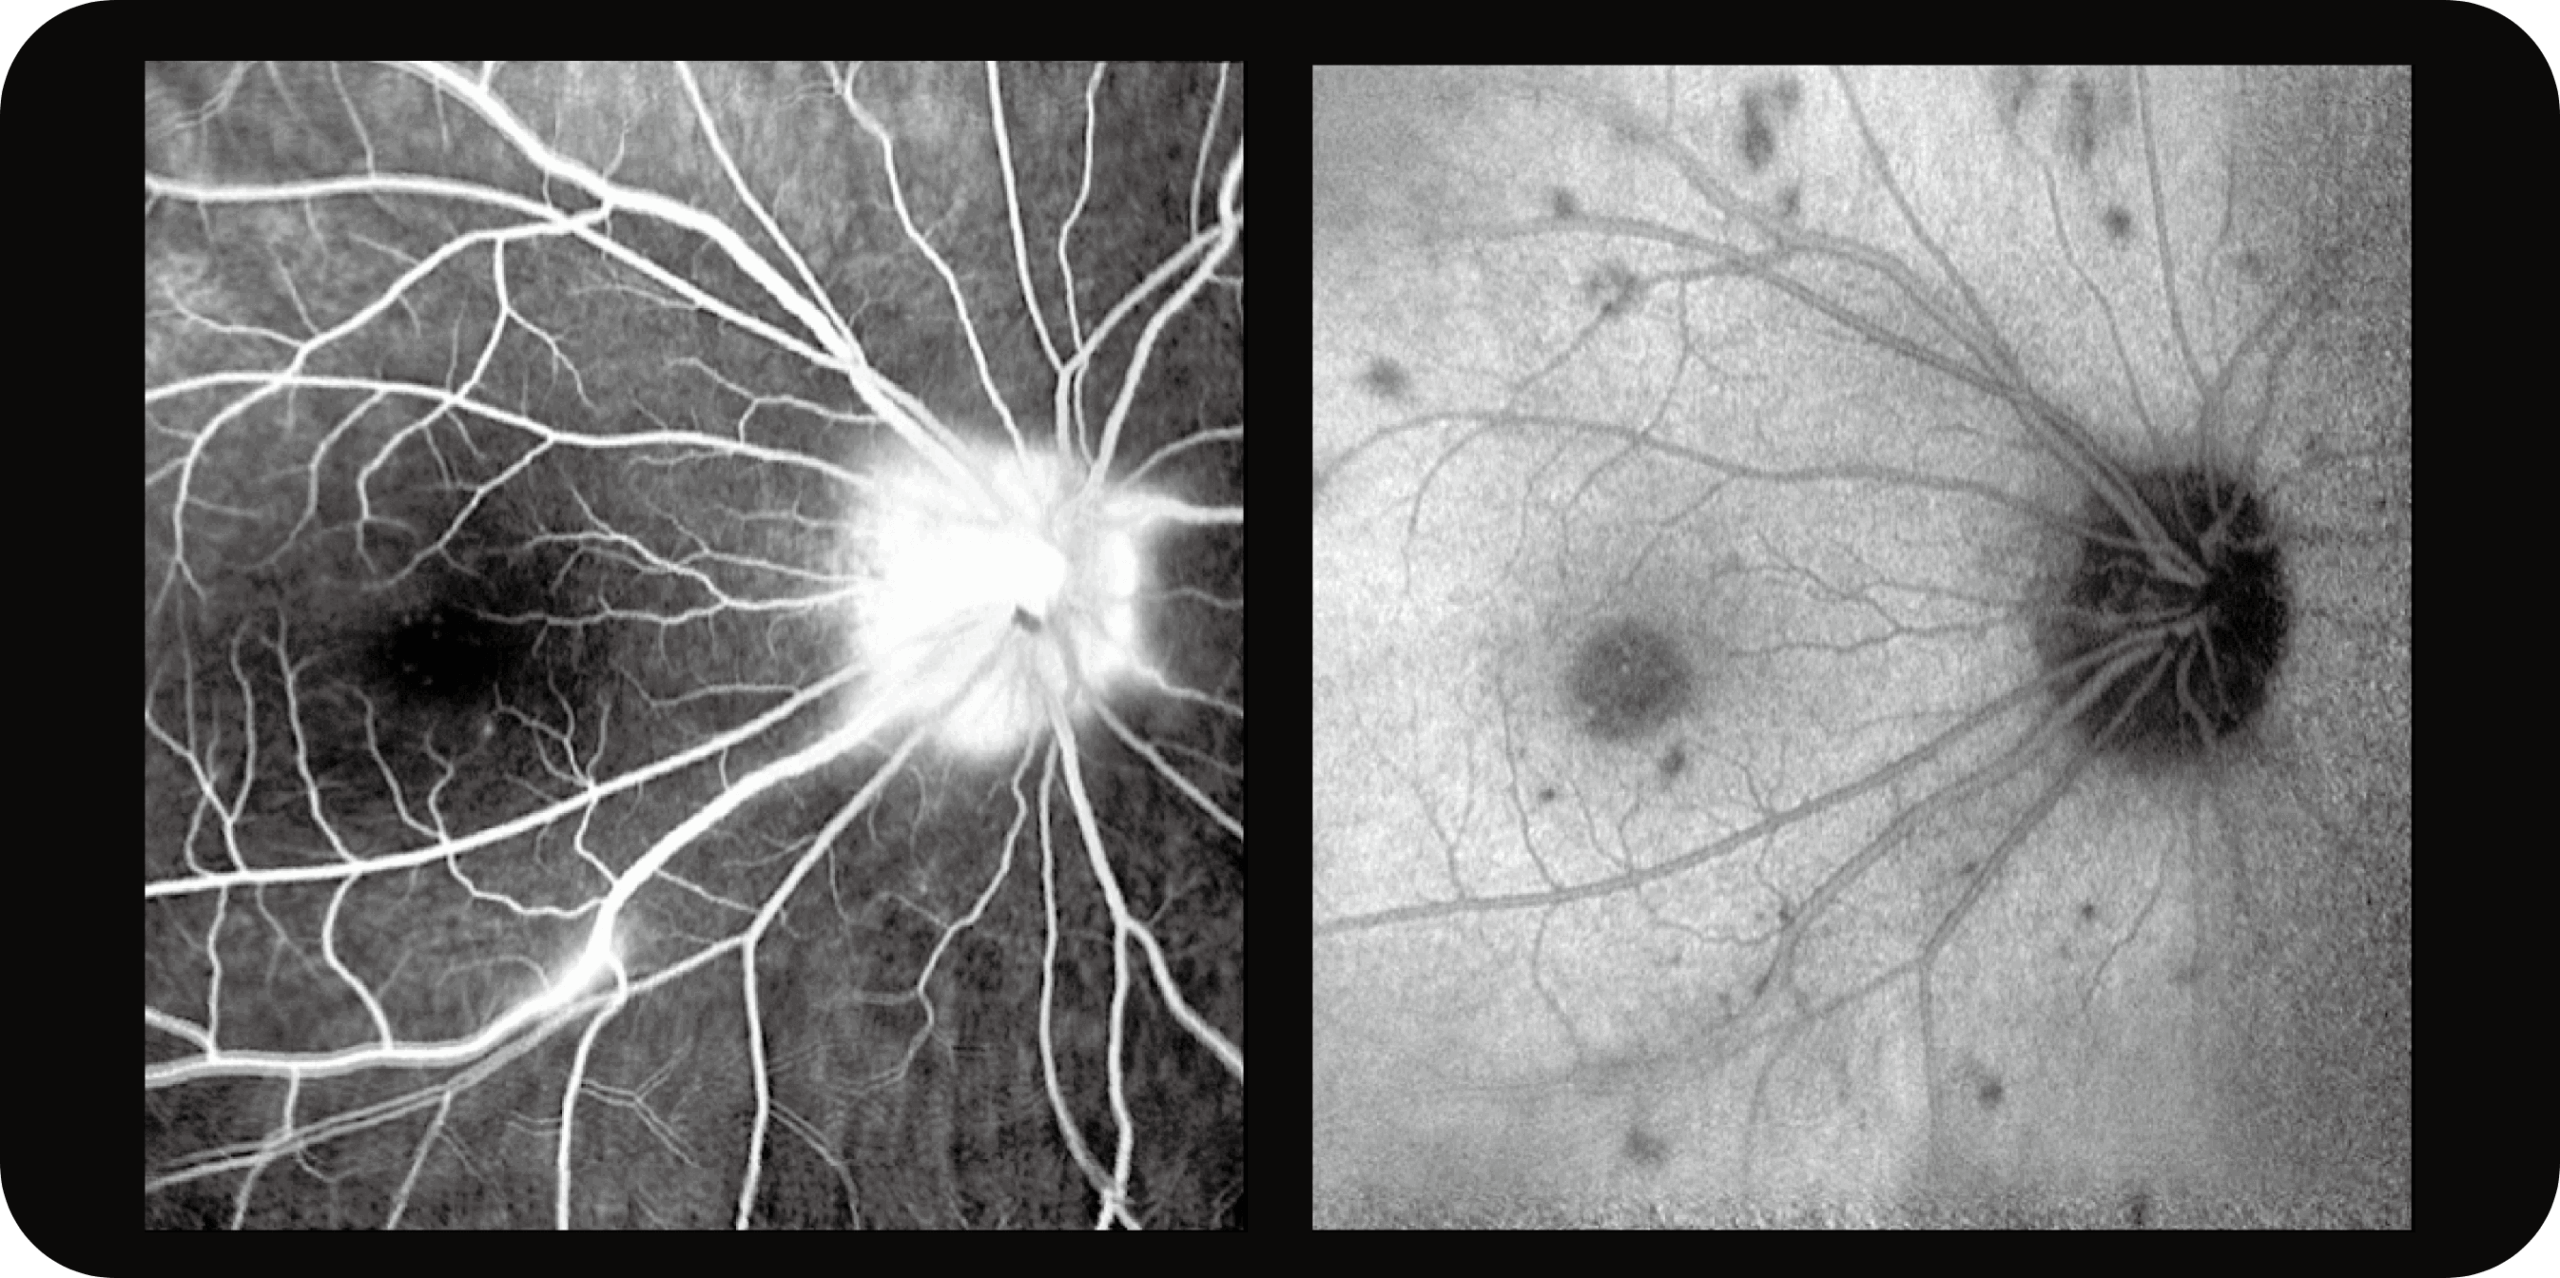

Multi-Modalidade

Altamente integrado com tecnologias como SLO confocal e SS-OCT, ele combina imagens coloridas SLO de campo ultralargo, angiografia confocal a laser, autofluorescência e imagens tomográficas de segmento anterior e posterior ultraamplas e profundas em um único sistema.

Angiografia multimodal (FA e ICG – disponível nas versões avançadas).

OCTA até 220° em mosaico, para análise detalhada da vascularização.